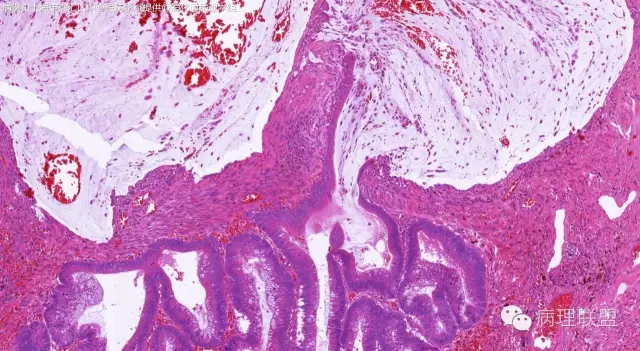

男,64岁,距肛门口45cm息肉大体:灰白结节2*2*1cm(病例由上海市徐汇区中心医院 李斌 提供,致谢!)

管状~绒毛状腺瘤伴低级别上皮内瘤变,黏膜下层部分腺体破裂黏液外溢伴黏液糊形成。

本例部分腺体异位到黏膜下层。

@李斌 李大夫的片子一向漂亮,有赏心悦目的感觉,必须赞一个。这例同意周大夫的意见,低级别绒毛管状腺瘤伴腺体破裂导致的黏液外溢。粘液池周围可见血管扩张淤血、含铁血黄素沉积、肉芽组织形成,提示发生过蒂扭转和出血,这常是造成假浸润、粘液溢出的原因。比较大的绒毛管状腺瘤会有分叶结构,会有比较粗大的平滑肌干,但缺少P-J息肉叶脉样从主干再分支出来的细平滑肌束。作为错构瘤性息肉的一种,P-J息肉的腺体可以分支、扩张、腺腔不规则,但没有细胞异型性,伴发异型增生时,局部出现细胞异型性但不会像这例这样齐刷刷都是异型的腺体。